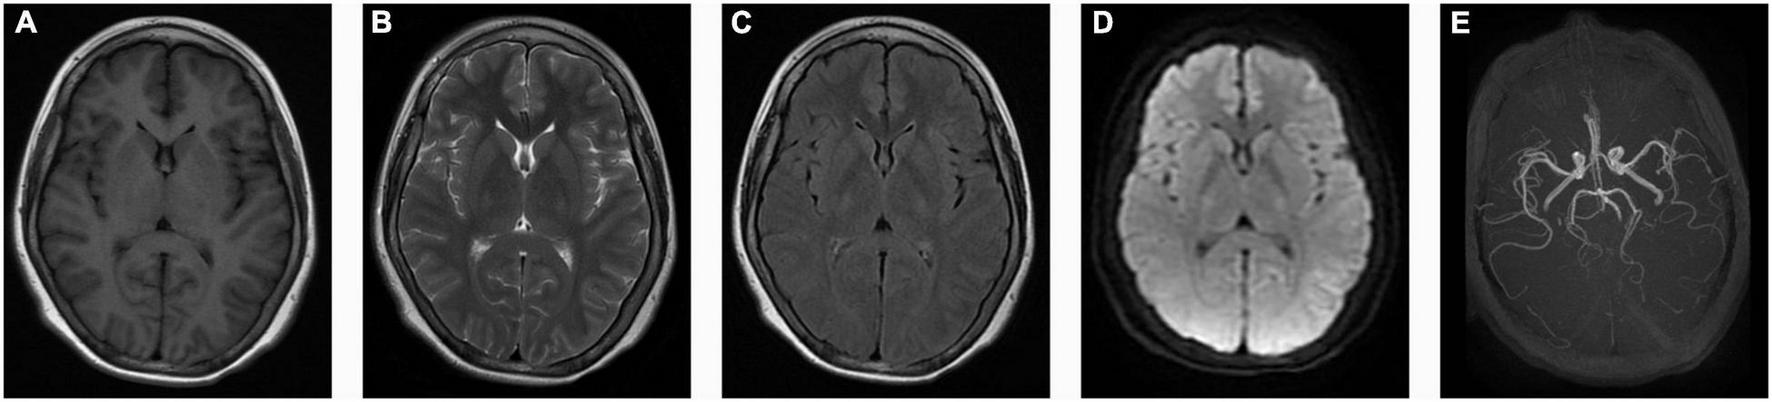

The cerebrospinal fluid (CSF) pressure was elevated to 285 mmH2O (normal range: 80–180 mmH2O, 1 mmH2O = 0.0098 kPa) when the headache was still present. The blood and CSF analysis of autoimmune encephalitis-related antibodies, oligoclonal bands, and paraneoplastic antibodies were negative. Electroencephalogram (EEG) showed full conductance diffuse of 1–3 HZ δ activity with left-right symmetry. Spinal cord and brain MRI and magnetic resonance angiography (MRA) showed no abnormalities (Figure 1). Electroneurogram is normal. The concentration of serum sodium and chlorine were slightly below the normal range when he was first admitted to the hospital, which returned to normal after sodium chloride supplementation. Serum magnesium was monitored for the patient with the range of 0.41–0.54 mmol/L (normal range: 0.70–1 mmol/L) during hospitalization. The random urine electrolyte test detected the concentration of magnesium (2.4 mmol/L), calcium (1.1 mmol/L), sodium (36.7 mmol/L), potassium (12.54 mmol/L), and chloride (31.7 mmol/L). Urinary magnesium excretion fraction (FEMg) was 9.7% (normal range: 2–4%). Serum parathyroid hormones are normal. No abnormality was found in blood and urine screening for genetic metabolic disease. The pedigree chart in this family was shown in Figure 2A.

FIGURE 1

No abnormalities in the patient’s brain MRI and magnetic resonance angiography (MRA). (A) Axial T1-weighted images (T1WI); (B) Axial T2-weighted images (T2WI); (C) Axial T2 fluid attenuated inversion recovery sequence images (Flair); (D) Diffusion-weighted imaging (DWI); (E) Magnetic resonance angiography (MRA) images.